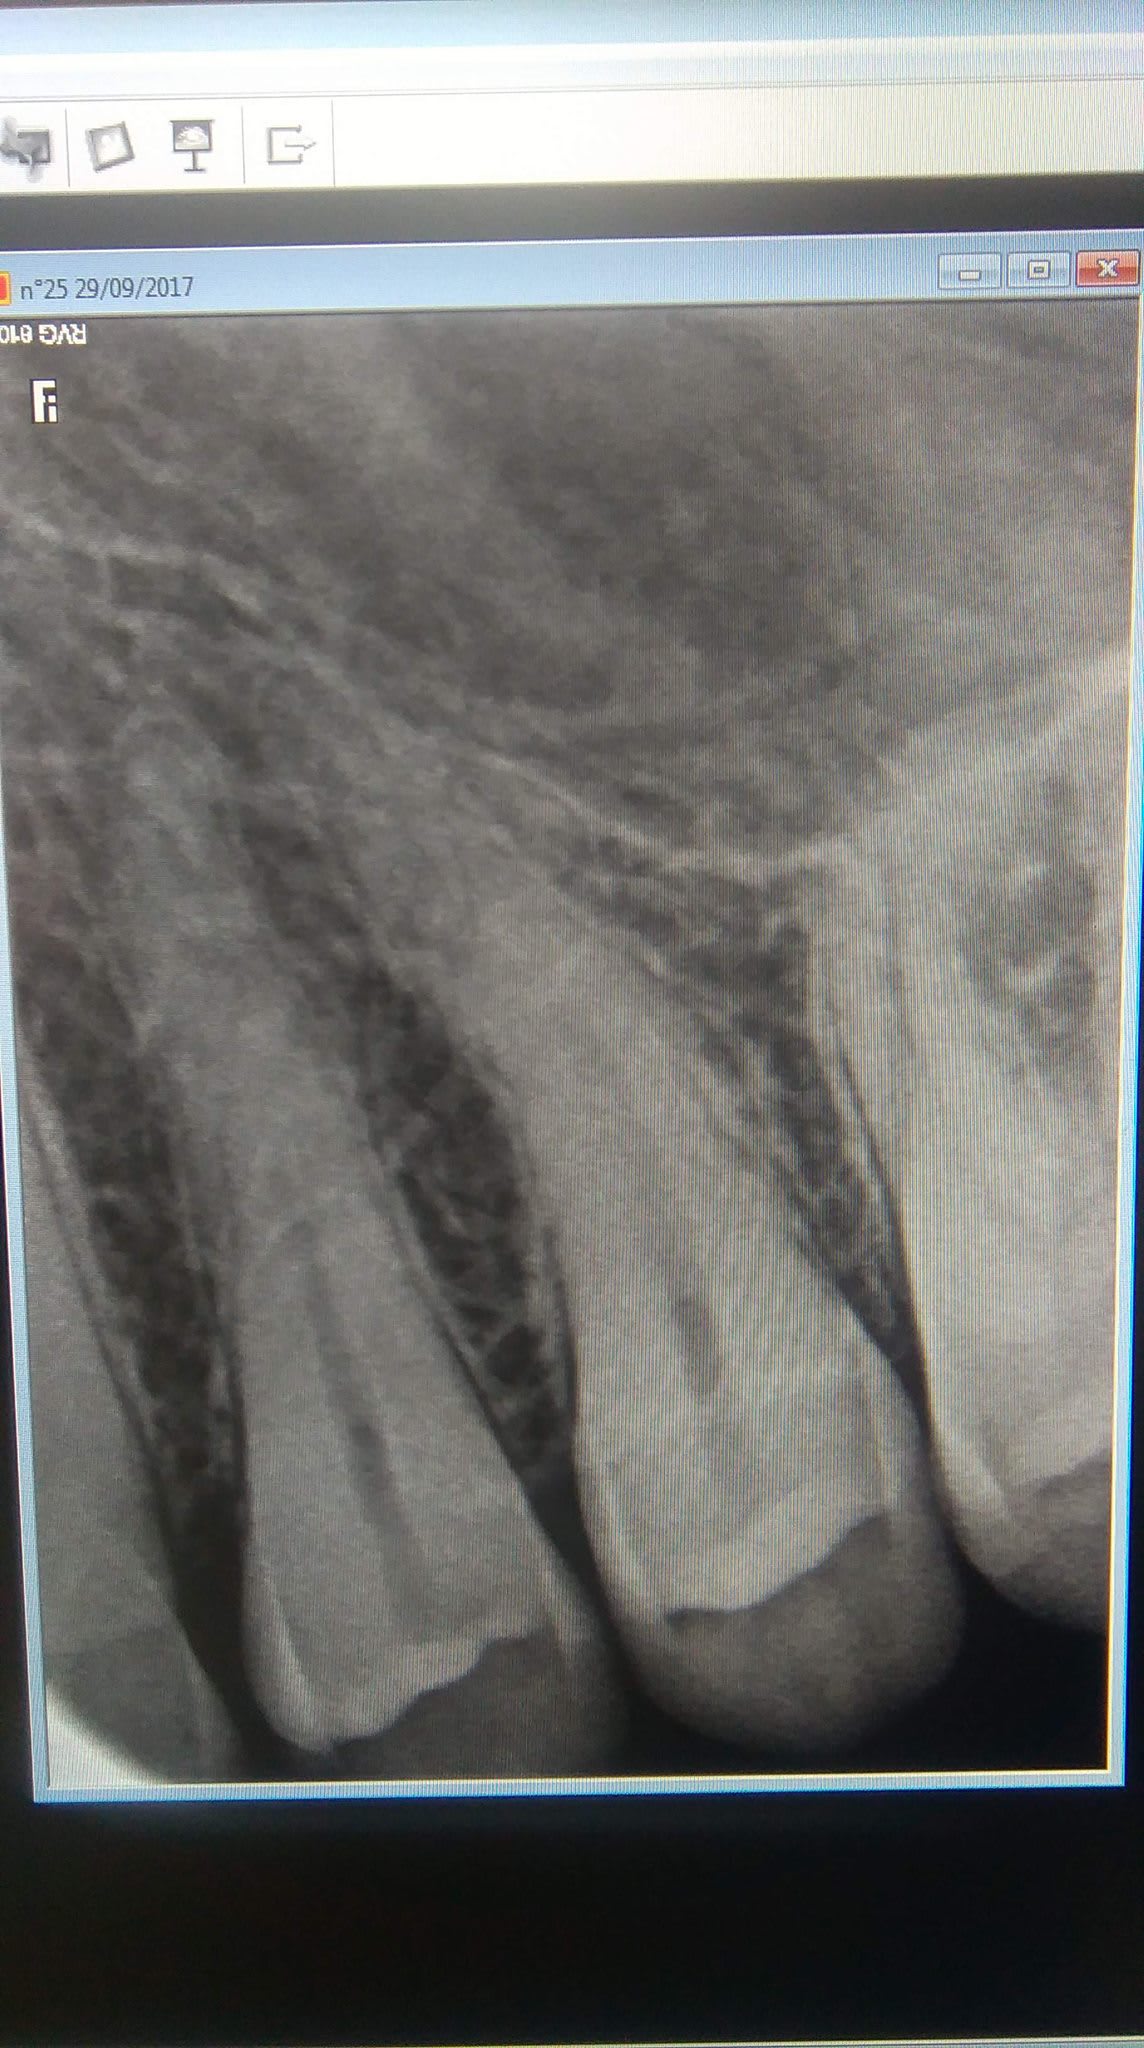

Désolé pour la qualité des radios (et photos), je ne sais pas si vous avez déjà eu un cas similaire.

Cette image radio du sinus ne peut-elle pas être en relation avec son opération dans l'enfance ?

les signes cliniques que tu décris évoquent la sinusite (pas forcément aigüe) par contre tes deux rétro ne permettent pas d'objectiver quoi que ce soit sur le sinus, excepté que les dents sont sinusiennes.